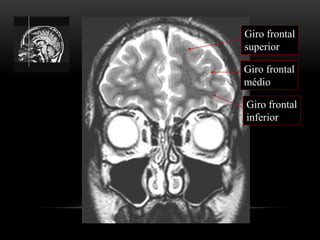

ANATOMIA TOPOGRÁFICA

Plano coronal

Giro frontal

superior

médio

inferior